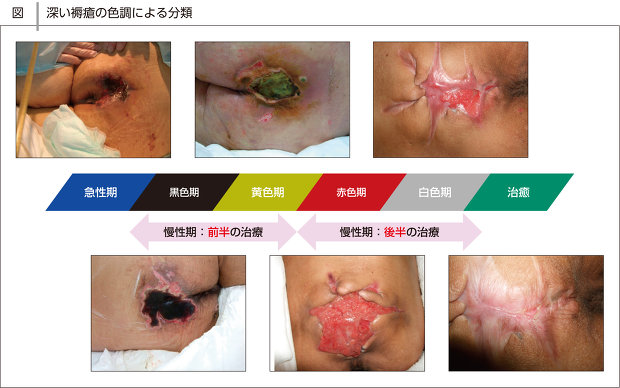

急性期の褥瘡と慢性期の褥瘡とは浅い褥瘡、深い褥瘡進展過程。

急性期の褥瘡と慢性期の褥瘡とは浅い褥瘡、深い褥瘡進展過程。

褥瘡の色でみる治癒分類 黒色期~白色期見て!わかる!病態生理と看護 花子のまとめノート。